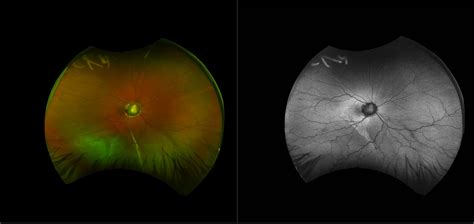

Morning Glory Syndrome, also known as morning glory disc anomaly, is a rare, unilateral—though sometimes bilateral—congenital defect of the optic nerve. It is named for its striking visual resemblance to the morning glory flower. In a healthy eye, the optic nerve head is typically pink, oval, or circular with a clearly defined rim. In contrast, an eye affected by this syndrome presents with an enlarged, excavated, funnel-shaped depression that disrupts the normal anatomy of the optic nerve.

• Excavated optic disc: A deep, white, or yellowish depression at the site where the optic nerve meets the retina.

• Peripapillary halo: A ring of depigmented, raised tissue surrounding the optic nerve head.

• Vascular abnormality: The retinal blood vessels typically emerge from the periphery of the disc rather than the center, appearing straightened and radiating outward like the spokes of a wheel.

• Central glial tuft: A white, grayish mass of tissue often sitting in the center of the excavation.

• Ophthalmoscopy: Direct visualization of the retina to identify the characteristic "flower-like" shape of the disc.